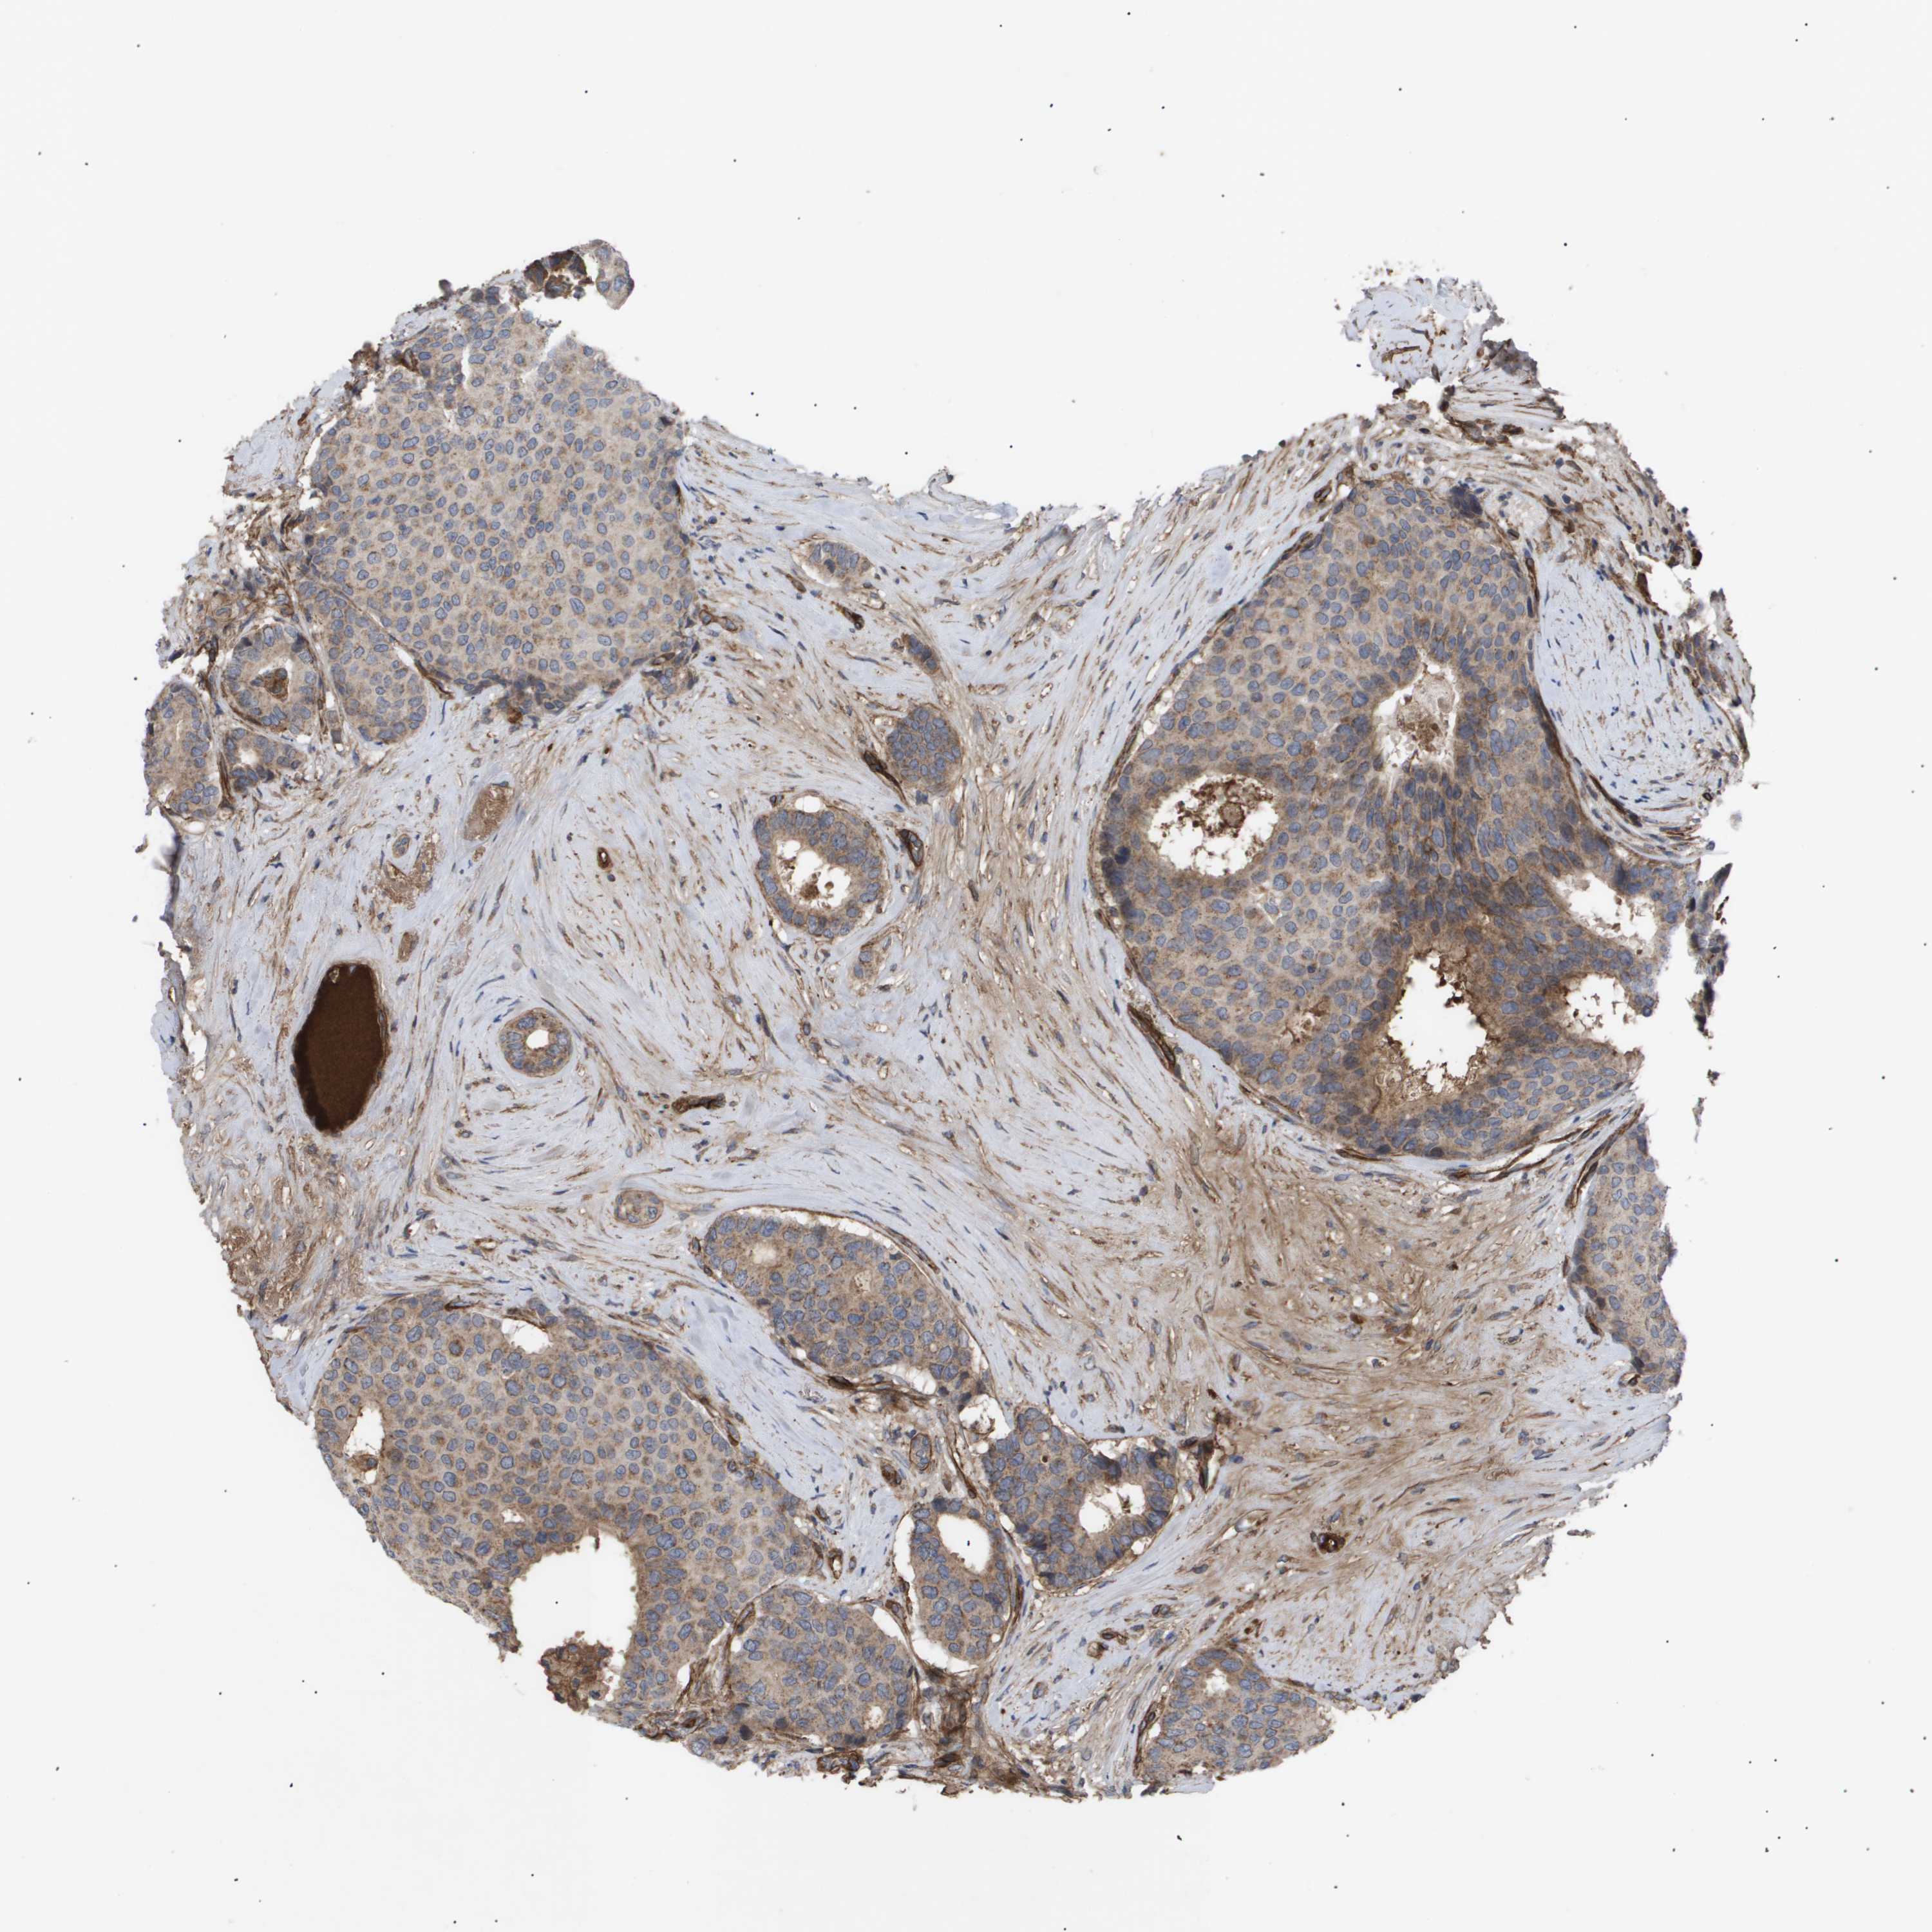

CANCER BREAST CANCER Show tissue menu

BRCA TCGA BRCA VALIDATION PROTEIN EXPRESSION